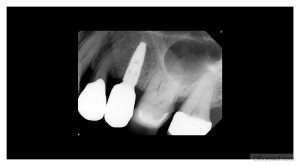

This 7-day hands-on course is designed for general dentists who want to begin performing the prosthetic phase of implant dentistry in Ontario, and meets the initial educational requirements as set out by the RCDSO.